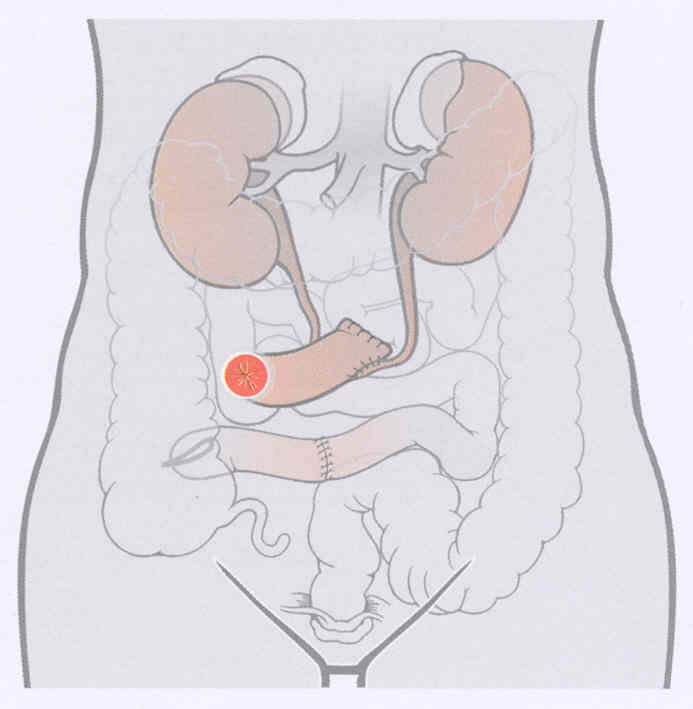

7 Bladder Cystectomy:

This operation is performed to eliminate a part of, or the whole urinary bladder, with patients identified with bladder cancer. The main risks for this operation are the maximum for an illness of the intestine that can cause the inflammation of the covering coating the abdomen. There is a danger for urine leakage from the bladder opening location.